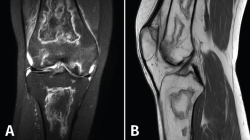

Figura 52. A: corte de secuencia coronal T2 Fat-Sat con infartos óseos en el fémur y la tibia; B: corte de secuencia sagital T1 con infartos óseos en el fémur y la tibia.

Los infartos medulares óseos aparecen en el 0,06% de los pacientes a quienes se les ha realizado una RM del aparato locomotor. Se presentan como lesiones segmentarias, puramente medulares, sin afección cortical, normalmente múltiples y que afectan predominantemente a los huesos largos de las extremidades, sobre todo las inferiores. La RM es esencial en el diagnóstico por imagen, apareciendo como lesiones óseas intramedulares de contornos serpiginosos hipo- o isointensos en secuencias T1 e hiperintensos en T2. Por tanto, la RM es el instrumento crucial en las fases iniciales, ya que permite caracterizar las lesiones y proceder a su diagnóstico temprano(19)(Figura 52).